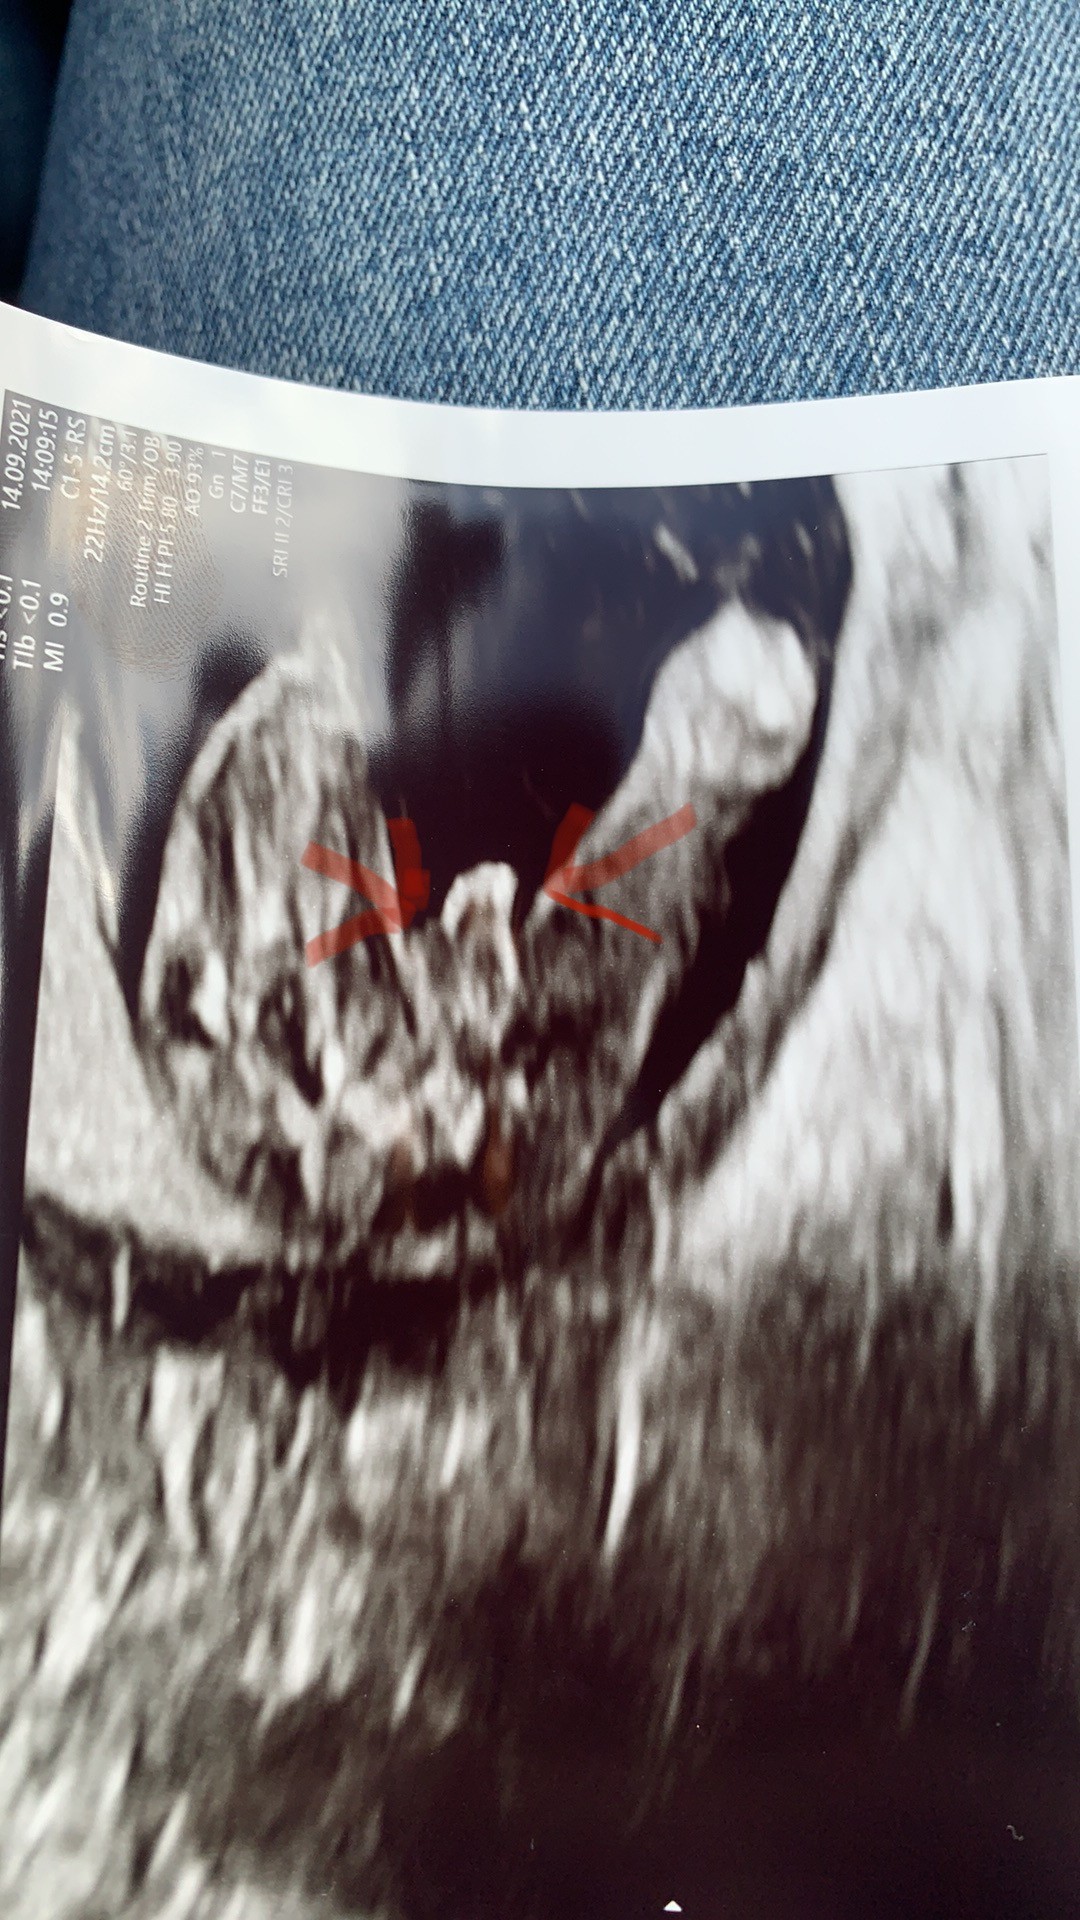

To wlasnie płeć dzieciatka:) wyglada na chlopczyka. Lekarz przy badaniu widzi wiecej niz my na jednym zdjeciu dlatego moze byc bardziej pewny w zgadywaniu czy to chlopczyk czy dziewczynka.

To to wielkie obok zaznaczonego co to jest? Bo już zgłupiałam 🤣 myślałam, ze to zaznaczone to może być warga sromowa, a to duże obok opuchnięta warga sromowa..

Chodzi mi o te dwie antenki 😜🤣